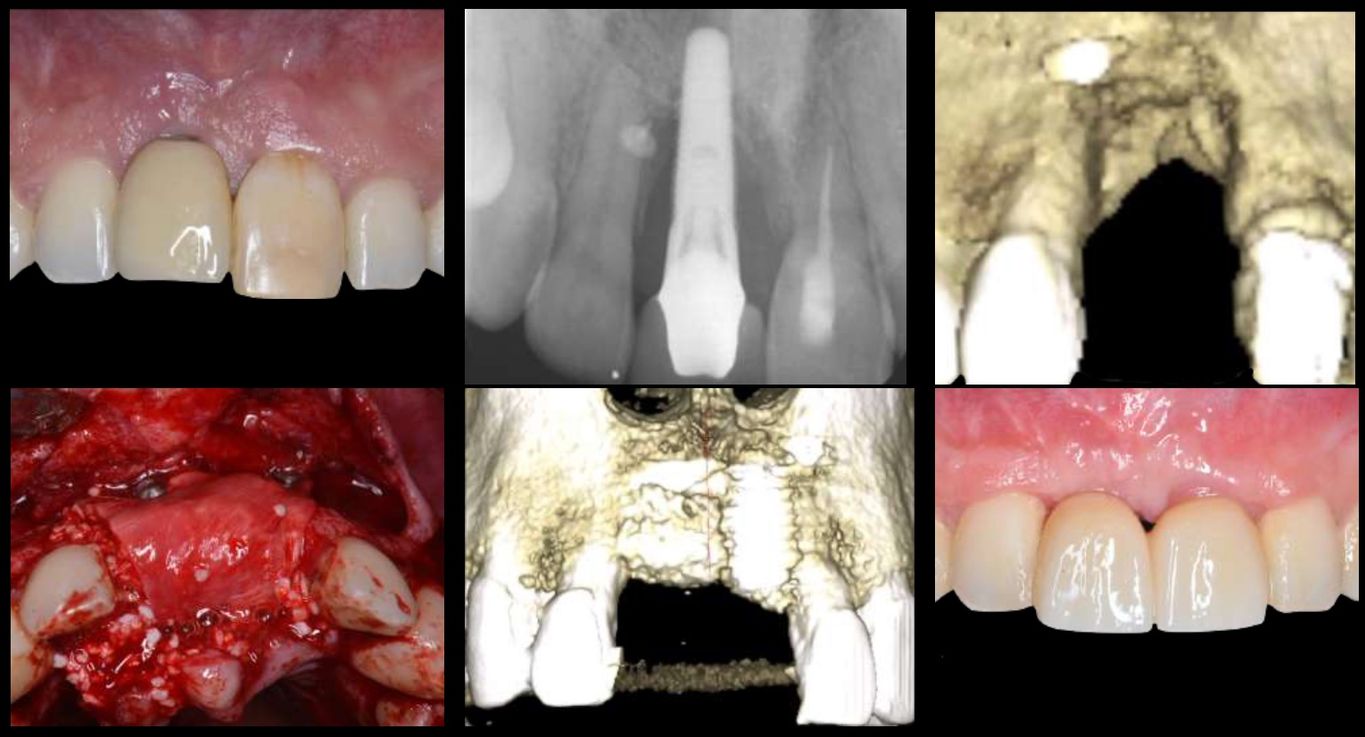

Cirugía Ósea Guiada: de la Teoría a la Práctica

En este curso aprenderás TODO sobre Regeneración Ósea Guiada (ROG)... desde los principios biológicos hasta la técnica quirúrgica PASO A PASO.

Tanto si estás iniciándote en este tipo de tratamientos, como si ya llevas haciéndolos años, si quieres hacer de tus ROG un tratamiento predecible y del que disfrutes cada vez que las hagas, ¡ESTE ES TU CURSO!